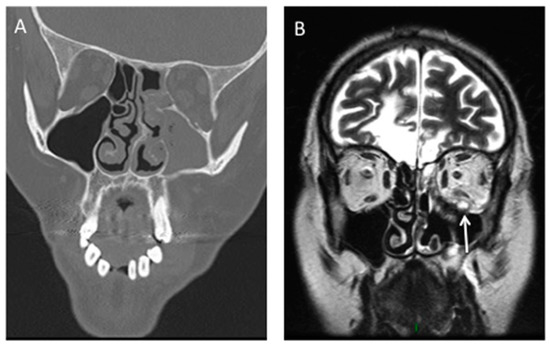

2. Rhino-Orbito-Cerebral Mucormycosis (ROCM)